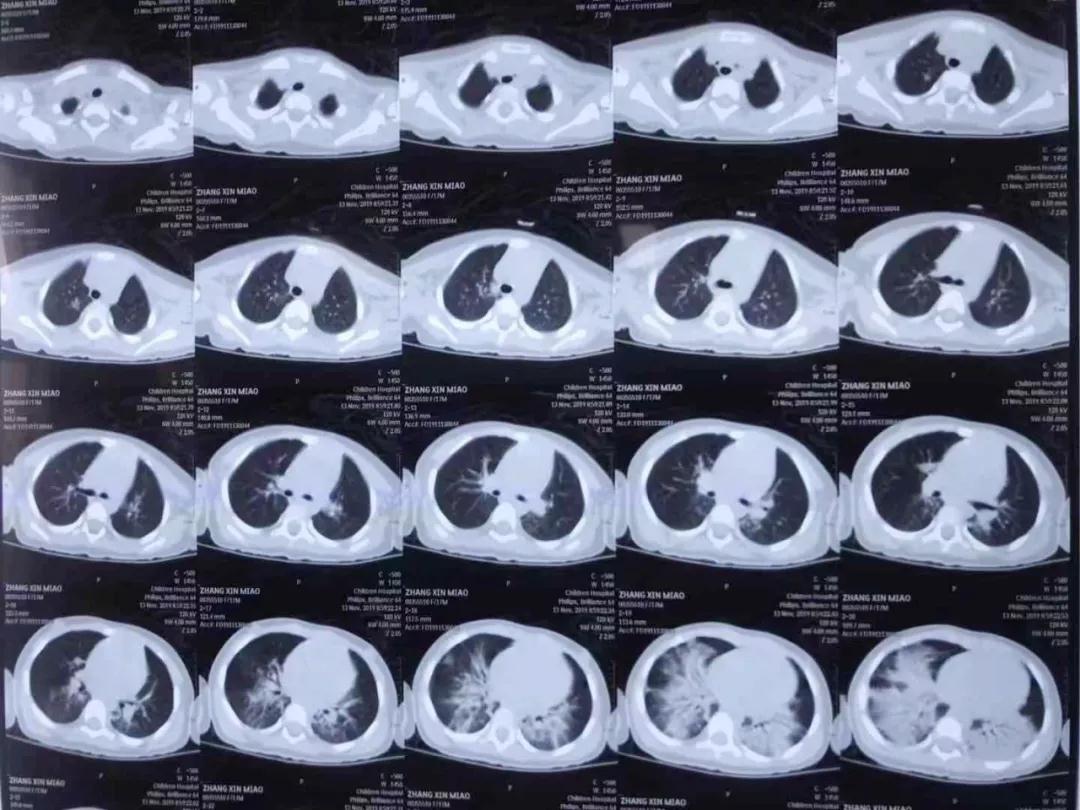

a片网站 PICU主任单立业说,苗苗来院时呼吸困难、意识淡薄直接进入重症监护室,经检查是洗衣有机溶剂中毒,造成急性肺水肿、急性肺损伤以及心肌损害,随即给予无创呼吸机通气,抗炎、保护脏器功能等综合治疗。

5天120个小时,专家协同会诊、抢救、稳定患儿生命体征直至脱离生命危险,在重症监护病房治疗一周后,苗苗身体各项指标好转,撤掉呼吸机,转到普通病房,11月26日早上,苗苗出院回家。